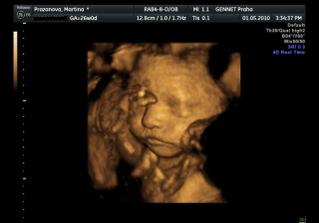

Určitě dám sem vědět i s aktuální fotečkou. Jména mám v pase. A 1.května jdeme na 4D UTZ, tak se moc těšíme 🙂

Letí to jak blázen, vždyť to znáš 🙂. Zatím nevíme nic, ale zítra jdeme na velký genetický UTZ, tak snad tam prcek nebude sedět v tureckém sedě jako minule 🙂))